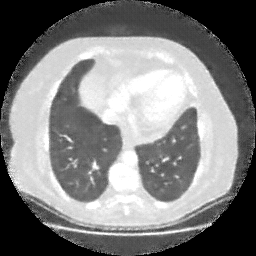

Original NATIVE CT scan (input)

No window - Raw intensity values

Lung window (WL -600, WW 1500 β†’ Low βˆ’1350, High +150)

Mediastinum window (WL 40, WW 400 β†’ Low βˆ’160, High +240)